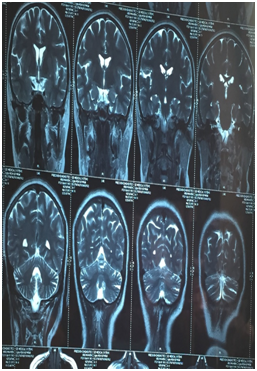

Biopsy of the breast revealed Infiltrating Ductal Carcinoma -Not Otherwise Specified- Grade II with ER Negative; PR weakly positive and Her-2neu Strongly positive (Figure 1). Metastatic work-up including, USG abdomen, CTabdomen&chest, Bone scans all turned out negative for metastasis. MRI brain was taken to rule out metastasis, which showed cerebellar atrophy with no evidence of metastasis (Figure 2). CSF analysis was done, which was normal with no abnormalities. Anti YO autoantibodies was sort which was strongly positive. As per our Tumor board policy patient received 4 cycles of Chemotherapy, as neoadjuvant therapy and the lump responded well to treatment and almost disappeared. The chemo regimen being 5-FU,Adriamycin and cyclophosphamide. The patient was put on a course of steroids. But the neurological symptoms progressed. Later the patient was operated, modified radical mastectomy was done (Figure 3). Post-op pathological report came as IDC-NOS in a small area. Yet the patient’s neurological symptoms progressed and became wheelchair bound.

Figure 2 MRI of the patient showing cerebellar atrophy.

MRI brain in the early stages will mostly be normal and in advanced stages may Show cerebellar  atrophy.8,9 This atrophic changes was seen in our patient. CSF analysis in the majority of PCD patients  shows lymphocytic pleocytosis and elevated protein level.10 In our patient the CSF analysis showed no  abnormality. As previously mentioned Anti YO levels will be detected in PCD which will be absent in otherwise normal  individual. It has been quoted that 40% of PCD presents with negative antibody status.11 It appears  negative antibody in PCD is a good prognostic feature. In our patient the antibody level was strongly  positive and the patient’s status deteriorated in spite of the measures. This was in accordance with some of  the previous literature.12